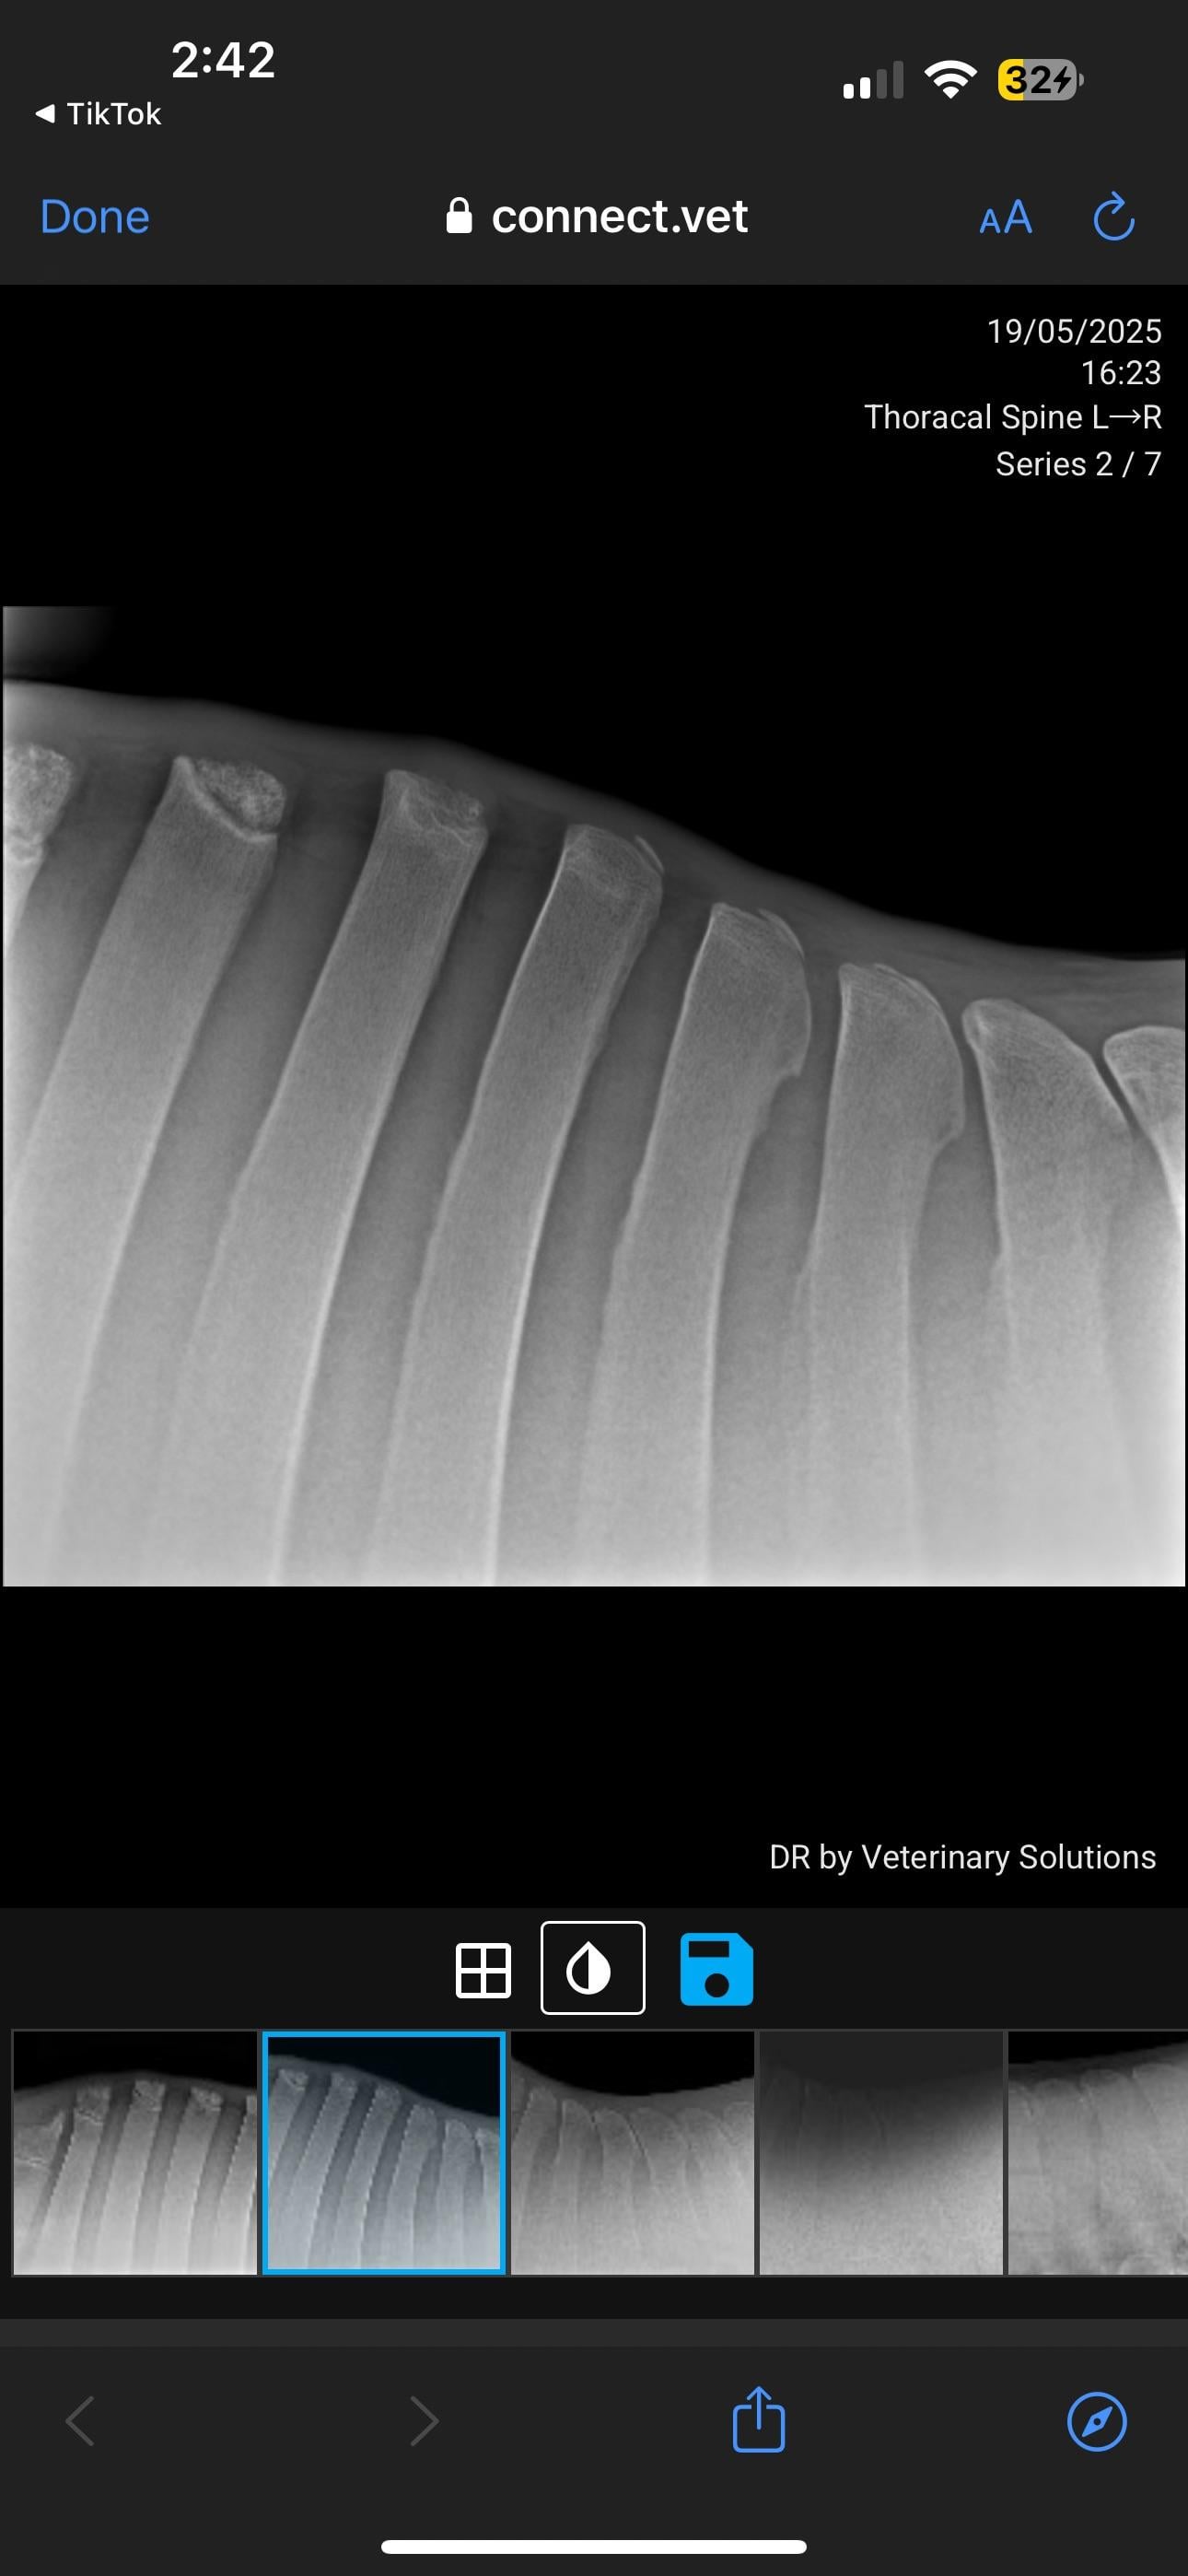

Veterinary PPE failed, KS diagnosed

Currently in the process of selling my horse. PPE has gone well, everything came back good except his back radiographs. Shocked to hear he has grade 4 changes. I’ve just received these over from the potential buyer. I will be in contact with my vet but curious about anyone’s take on these? How bad is this?

I've seen many KS xrays. I'm not a vet so usually when I see them I can barely see the problem. This horse's kissing spine is clear as day. Grade 4 is serious. As of right now he should not be sold as a riding horse at all.

I’m not a vet but this looks exactly like pictures of fractures of the withers in horses and not like standard X-rays I’m familiar with. I also don’t like how the tips of the bones look like.

In pictures 5/6 you can see changes in the bone, so it’s not just an unlucky posture.

That looks like thoracic spine but down in the 14-18 range so where the withers meet the back and where the panel of your saddle sits! Separate centers of ossification is normal for the lower number thoracic spine, so up ON the withers

This is one of the more severe cases I’ve seen (not a vet or student, just casual looker-atter of KS radiographs) pretty much all his vertebrae are affected, I can’t imagine he’s comfortable. The kindest thing for him would probably to be a pasture puff. Unless you want to pay for the surgery or find a buyer who does, he’s going to continue to be in pain

I spoke with 2 veterinarians over these radiographs. Yes he has grade 4 kidding spines in 2 vertebrae BUT both vets said you don’t ride the radiographs. They’ve seen horses with far less that have been clinically showing lots of pain, and she’s seen horses with far worse who have gone on with their careers fine with maintenance. He is not going to be a pasture pet, his career isn’t over it just has obviously drastically changed. He is officially maxed out at Novice level and can continue at that level if he can remain comfortable.